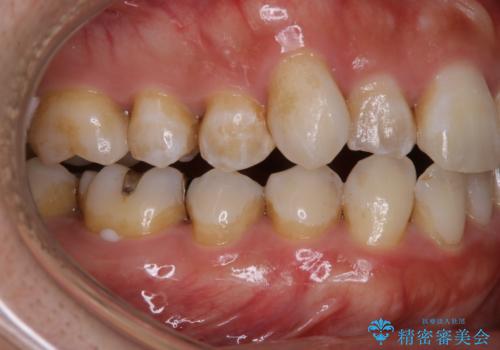

放置した虫歯 歯ぐきの中まで虫歯でも、しっかり健康的な部分を引っ張り出して、きちんと処置します。